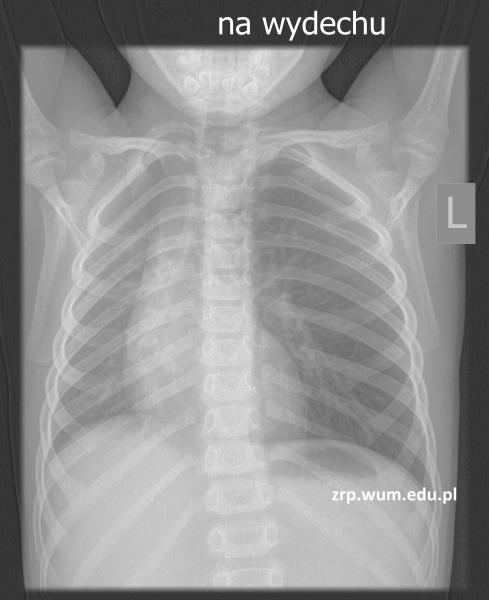

Przypadek 13: 4-letni pacjent z podejrzeniem aspiracji ciała obcego do dróg oddechowych, stan po zakrztuszeniu się marchewką.

Rozpoznanie: W badaniu RTG klatki piersiowej wykonanym standardowo, na wdechu - bez zmian, cieniującego ciała obcego nie uwidoczniono. Dodatkowe zdjęcie wykonane na wydechu uwidoczniło masywne rozdęcie lewego płuca z przemieszczeniem śródpiersia na stronę prawą - cechy RTG pułapki powietrznej, pośredni objaw obecności ciała obcego powodującego niedrożność lewego oskrzela. Pacjent skierowany na bronchoskopię.